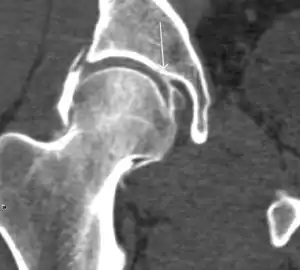

MRI has been shown to have 100% sensitivity and specificity in prospective studies of occult hip fractures. These fractures were diagnosed by bone marrow edema and a low signal fracture line, mainly on T1 or T2 weighted images (Figure 10).[1]

Figure 10:

Stress femoral neck fracture in a young athlete barely visible in X-ray film as a sclerotic line (arrow)[1]

In this case, Tc 99 scintigraphy shows a band of uptake[1]

Furthermore, T1 (left) and DP fat saturated (right) weighted MR images showed the fracture line and a pattern of edema.[1]

Bone scanning in people with hip pain can be complementary to other imaging studies, mainly in indeterminate bone lesions to clarify whether it is an active lesion with abnormal radiotracer accumulation. Nevertheless, MRI has replaced scintigraphy in the diagnosis of most of these conditions. An example is stress or insufficiency fractures: increased uptake is usually present in around 80% of fractures within 24 h, and 95% of fractures reveal activity by 72 h following trauma, showing an overall sensitivity of 93% and specificity of 95%. MRI is superior to bone scans in terms of sensitivity (99%-100%) and specificity (100%). Moreover, a bone scan does not provide detailed anatomical location of the fracture, and further imaging is usually required.[1]